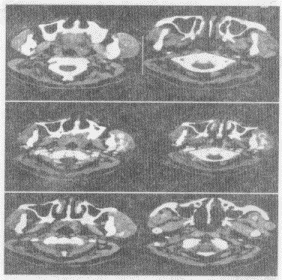

5.女,14岁,发现左侧耳前肿大3个月余,PE:左颊部耳前弥漫性隆起,无压痛,CT如图所示,最可能的诊断是![]() |

| 正确答案:E |